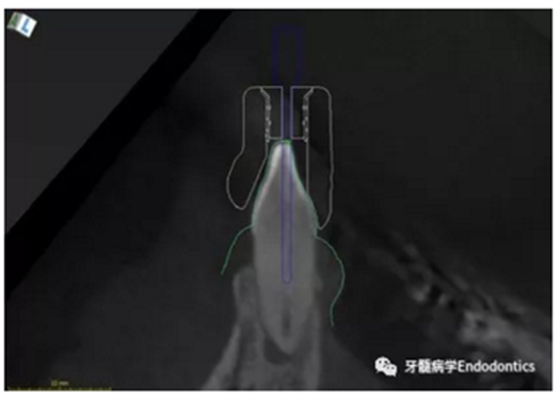

31、41叩痛明顯,牙冠變色(圖1)。溫度和牙髓電活力測(cè)試無反應(yīng)。兩張從不同角度拍攝的x線片顯示,相對(duì)于側(cè)切牙,雙側(cè)下中切牙都有嚴(yán)重的根管鈣化(圖2)。41有明顯根尖周暗影,31根尖周暗影不明顯。為進(jìn)一步證實(shí)31是否存在根尖周病變,同時(shí)精細(xì)觀察31、41的復(fù)雜結(jié)構(gòu),根據(jù)歐洲牙髓病學(xué)會(huì)CBCT應(yīng)用指南(2014),對(duì)患牙拍攝小視野、高分辨率CBCT。CBCT影像證實(shí)31、41均伴有根尖周炎和嚴(yán)重的根管鈣化(圖3)。距離根尖4mm可見根管影像。 由于患牙根管解剖結(jié)構(gòu)較為復(fù)雜,筆者決定使用特殊設(shè)計(jì)的微型鉆頭(直徑0.85mm)進(jìn)行“數(shù)字化導(dǎo)航牙髓治療”。 因此對(duì)下頜進(jìn)行口內(nèi)掃描(圖4)。用coDiagnostixTM軟件(Dental Wings Inc.,Montreal,Canada)將CBCT和口內(nèi)掃描的數(shù)據(jù)進(jìn)行處理,該軟件主要用于引導(dǎo)種植。通過該軟件對(duì)兩個(gè)掃描圖像進(jìn)行疊加后,虛擬鉆頭尖端沿牙長軸對(duì)準(zhǔn)根管下段可見部分(圖5)。三維檢查虛擬鉆的正確位置。

圖5.虛擬設(shè)計(jì)的微創(chuàng)根管入路。虛擬鉆針的尖端能到達(dá)鈣化根管X線影像中的可見部分。